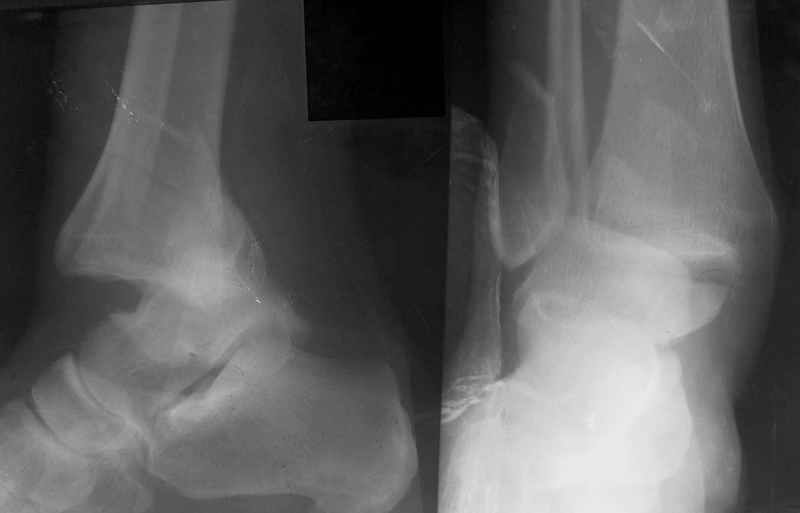

>>Это первый мой опыт лечения таких переломов в аппарате Илизарова...

>>ПХО раны, скелетное вытяжение на шине Белера. Через неделю наложен АВФ, устранен вывих стопы...

Ответы на вопросы: 1. Дистракцию снять! Все правильно вы понимаете: наружная лодыжка -ключ г\ст сустава, а пытаетесь наоборот - таранную кость сделать "ключом"... Нейротрофические расстройства очень могут появиться..

2. Конечно аппарат собран не лучшим образом. База на стопе очень низко расположена, есть даже сомнения: обе ли спицы проходят через пяточную кость? Откройте любое руководство по чрескостному остеосинтезу и найдете ответ на вопрос, как компоновать аппарат, возможно, даже удивитесь, когда узнаете , что есть компановки вообще не фиксирующие г\ст сустав.

3. Если добиваться в аппарате, то только путем проведения дополнительных спиц и небольшого перемонтажа... Диастаз говорит только о неанатомичной репозиции лодыжки, со всеми вытеающими...

Вообщем, еще не поздно (и совершенно неопасно) снять аппарат, и сделать открытую репозицию и полноценный остеосинтез наружной лодыжки стягиваающим винтом и нейтрализующей 1\3-трубчатой пластиной... Лучше это было сделать сразу при поступлении в качестве экстренной операции, крнечно если есть возможность, а она всегда будет, если есть желание!!